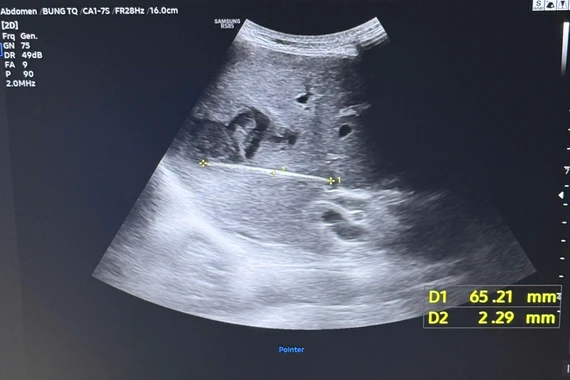

Điển hình là trường hợp bệnh nhân nữ 40 tuổi, trú tại xã Tiên Lương, tỉnh Phú Thọ. Bệnh nhân được đưa đến Trung tâm Y tế khu vực Cẩm Khê trong tình trạng mệt lả, choáng váng, da xanh, niêm mạc nhợt, mạch nhanh nhỏ khó bắt, huyết áp tụt 80/50 mmHg.

Ngay lập tức, bệnh nhân được các y bác sĩ khoa Cấp cứu và Sản khoa thăm khám, đánh giá và triển khai các biện pháp hồi sức tích cực. Bệnh nhân được chẩn đoán xác định: Chửa ngoài tử cung vỡ, trụy mạch.

Người bệnh được chỉ định phẫu thuật nội soi cấp cứu, tiến hành cắt khối chửa ngoài tử cung, cầm máu, đồng thời hút ra hơn 700ml máu trong ổ bụng.

Ca phẫu thuật cấp cứu bệnh nhân - Ảnh BVCC